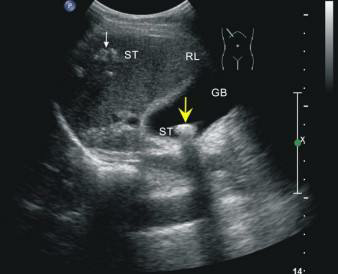

這位先生姓錢,自訴飲酒后出現(xiàn)胸骨后疼痛4小時(shí),呈壓榨性,持續(xù)不緩解,伴大汗、面色蒼白、惡心、欲吐,既往無(wú)高血壓、糖尿病、冠心病病史,吸煙史30年,偶有飲酒,入院時(shí)查體血壓為120/80mmHg,心率:98次/分,節(jié)律規(guī)整,未聞及明顯雜音。心電圖:竇性心律,心率98次/分,II、III、aVF導(dǎo)聯(lián)病理性Q波,ST段下移,不正常心電圖。不除外急性心肌梗死。急檢心肌酶及超敏肌鈣蛋白、淀粉酶,結(jié)果回報(bào)心肌酶、超敏肌鈣蛋白無(wú)明顯改變。疼痛時(shí)復(fù)查心電圖較前無(wú)變。胸痛癥狀仍持續(xù)不緩解,給予曲馬多止痛不改善。請(qǐng)示李桂武主任醫(yī)師,主任給予詳細(xì)詢問(wèn)病史、癥狀及查體,患者膽囊區(qū)有壓痛無(wú)反跳痛,考慮患者可能存在膽囊性疾病,不排除腎結(jié)石,指示:急檢肝膽胰脾彩超及泌尿系彩超。我急忙陪著患者及家屬去門診彩超室做肝膽胰脾及泌尿系彩超。結(jié)果如下圖。提示膽囊結(jié)石。

請(qǐng)肝膽外科梁博主任會(huì)診后建議行CT檢查以進(jìn)一步明確診斷,肝膽胰脾CT結(jié)果可見(jiàn)膽囊不大,內(nèi)見(jiàn)高密度結(jié)節(jié),約10mm(IM33),膽總管無(wú)擴(kuò)張。建議轉(zhuǎn)入肝膽外科行手術(shù)治療。